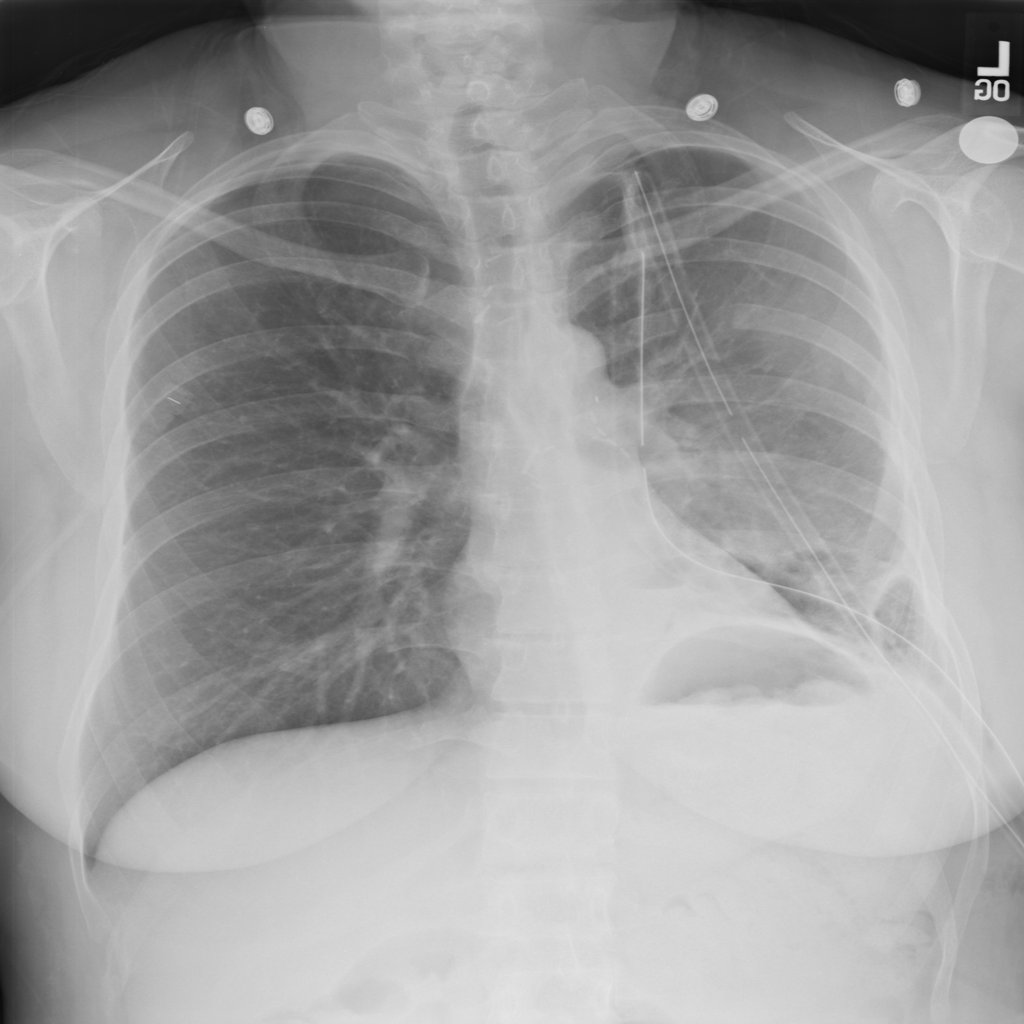

PAT-4639 · IMG-012Pneumothorax

PAT-4639 · IMG-012

AP